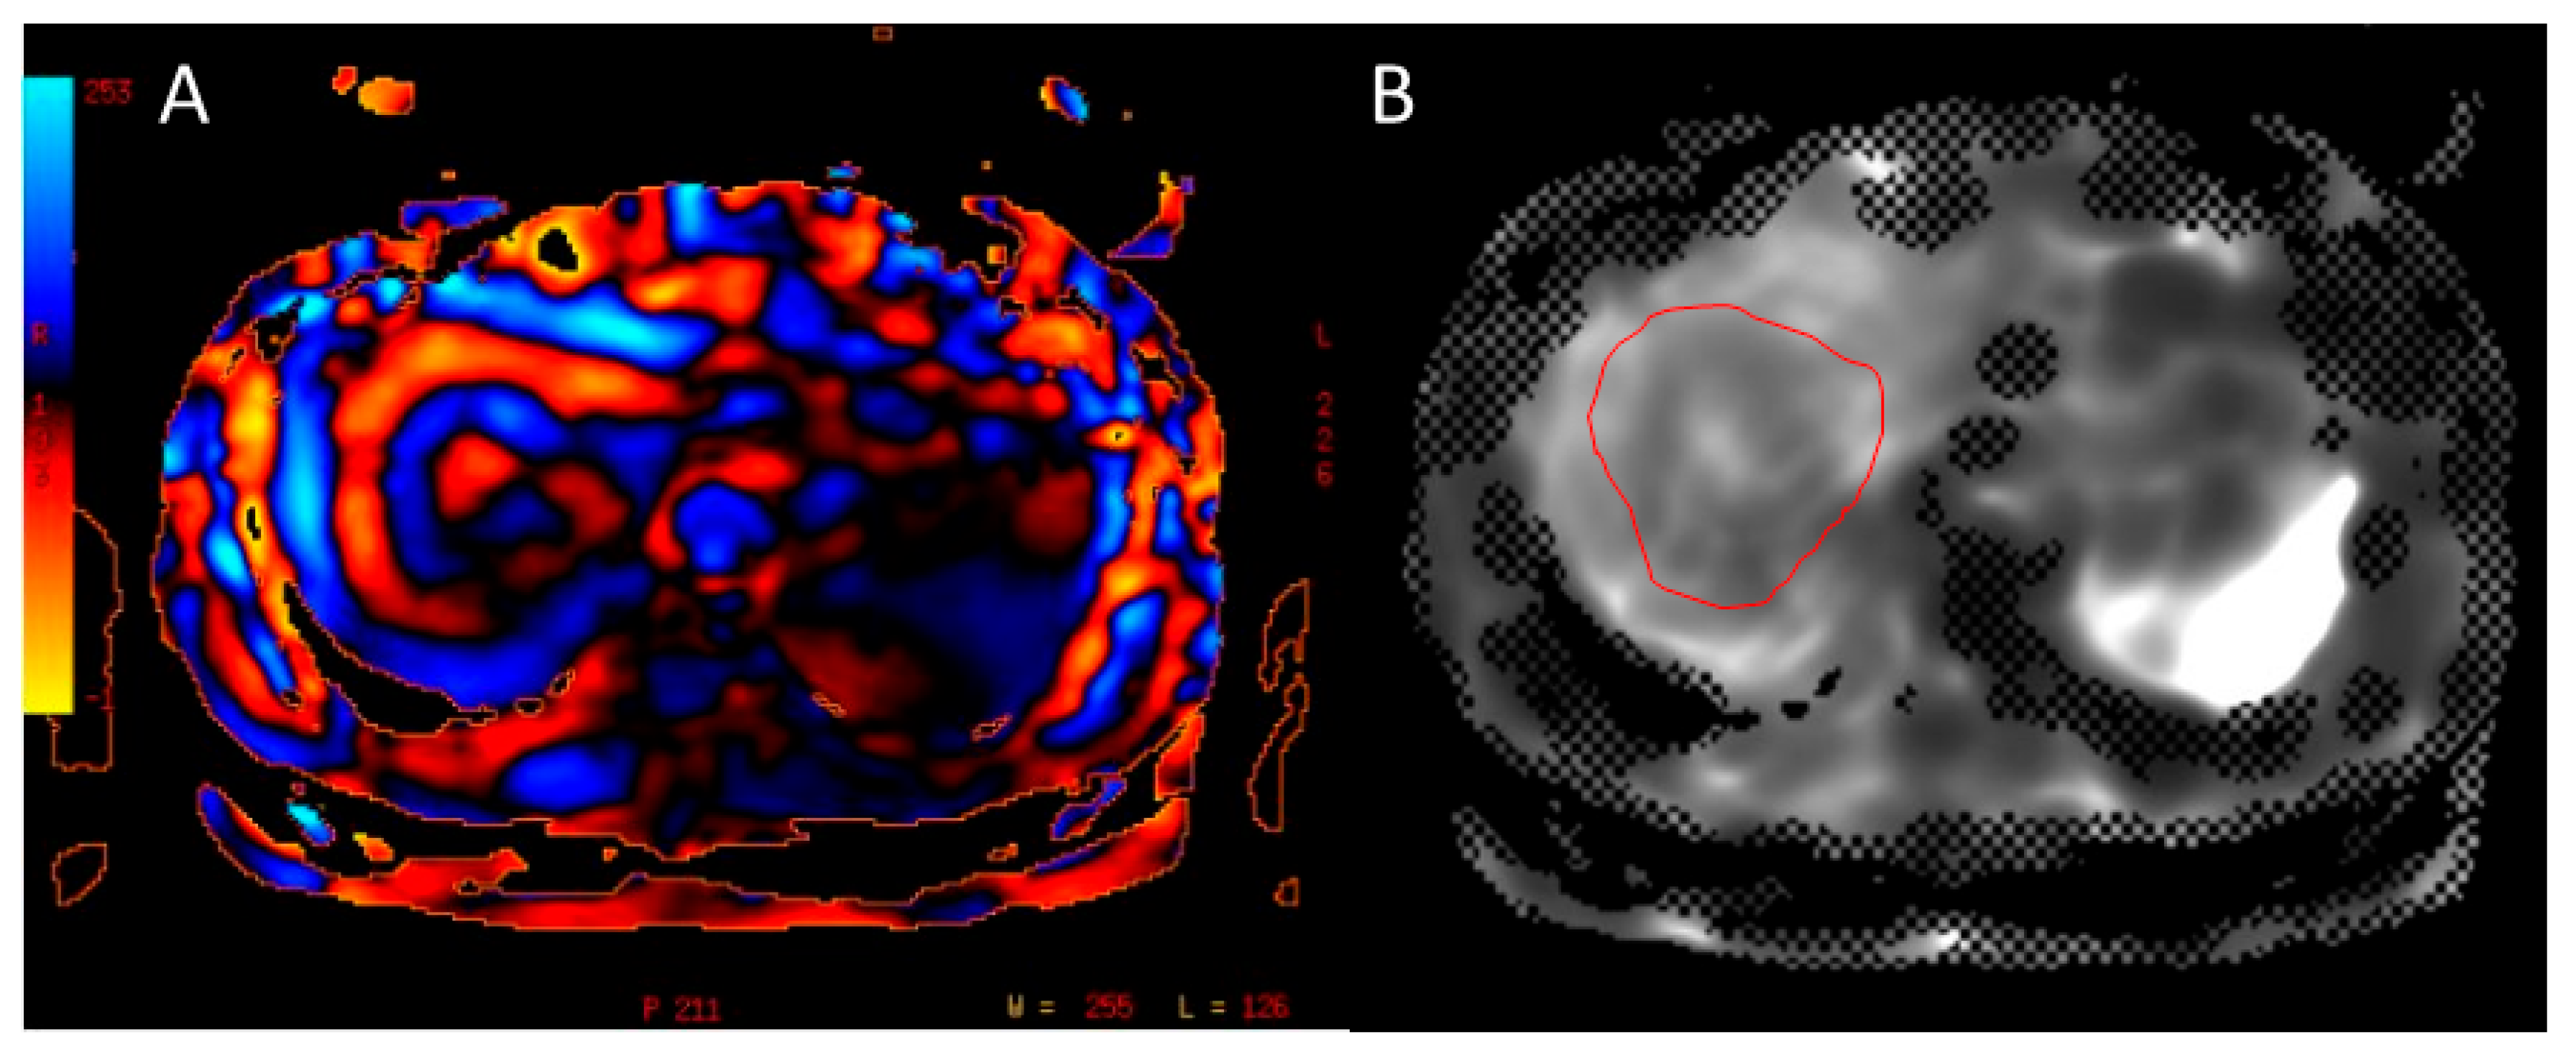

3.4. Extracellular Volume Fraction (ECV)

3.5. Extracellular Volume Fraction (ECV)

- Tago, K.; Tsukada, J.; Sudo, N.; Shibutani, K.; Okada, M.; Abe, H.; Ibukuro, K.; Higaki, T.; Takayama, T. Comparison between CT volumetry and extracellular volume fraction using liver dynamic CT for the predictive ability of liver fibrosis in patients with hepatocellular carcinoma. Eur. Radiol. 2022, 32, 7555–7565. [Google Scholar] [CrossRef] [PubMed]

- Shinagawa, Y.; Sakamoto, K.; Sato, K.; Ito, E.; Urakawa, H.; Yoshimitsu, K. Usefulness of new subtraction algorithm in estimating degree of liver fibrosis by calculating extracellular volume fraction obtained from routine liver CT protocol equilibrium phase data: Preliminary experience. Eur. J. Radiol. 2018, 103, 99–104. [Google Scholar] [CrossRef] [PubMed]

- Mizuno, M.; Tago, K.; Okada, M.; Nakazawa, Y.; Arakane, T.; Yoshikawa, H.; Abe, H.; Matsumoto, N.; Higaki, T.; Okamura, Y.; et al. Extracellular volume by dual energy CT, hepatic reserve capacity scoring, CT. volumetry and Transient-elastographyfor estimating liver fibrosis. Sci. Rep. 2023, 13, 22038. [Google Scholar] [CrossRef]